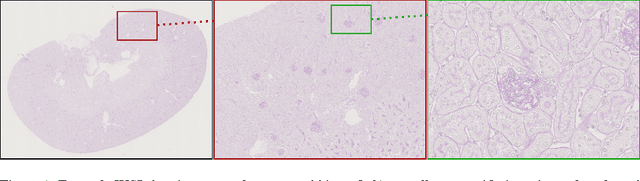

Abstract:Due to the increasing availability of whole slide scanners facilitating digitization of histopathological tissue, there is a strong demand for the development of computer based image analysis systems. In this work, the focus is on the segmentation of the glomeruli constituting a highly relevant structure in renal histopathology, which has not been investigated before in combination with CNNs. We propose two different CNN cascades for segmentation applications with sparse objects. These approaches are applied to the problem of glomerulus segmentation and compared with conventional fully-convolutional networks. Overall, with the best performing cascade approach, single CNNs are outperformed and a pixel-level Dice similarity coefficient of 0.90 is obtained. Combined with qualitative and further object-level analyses the obtained results are assessed as excellent also compared to recent approaches. In conclusion, we can state that especially one of the proposed cascade networks proved to be a highly powerful tool for segmenting the renal glomeruli providing best segmentation accuracies and also keeping the computing time at a low level.